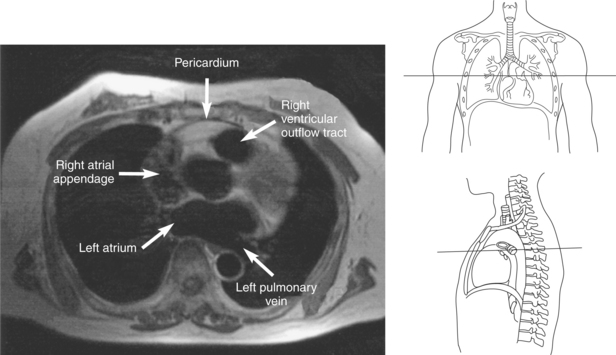

The right atrium forms the right border of the heart and receives deoxygenated blood from the body via the superior and inferior venae cavae and from the coronary sinus and cardiac veins that drain the myocardium. A small muscular embryonic appendage, the right auricle, projects upward and toward the left from the right atrium, covering the root of the aorta (Figure 6.40). The right ventricle lies on the diaphragm and comprises the largest portion of the anterior surface of the heart. It receives deoxygenated blood from the right atrium and forces it into the pulmonary trunk for conveyance to the lungs. Projecting off the inferior surface of the ventricular walls are conical-shaped projections of cardiac muscle called papillary muscles that anchor the cusps of the tricuspid valve to the right ventricle (Figure 6.39). The left atrium lies posterior to the right atrium and is the most posterior surface of the heart. It also has an embryonic appendage, the left auricle, that projects to the left of the pulmonary trunk over the superior surface of the heart. The left atrium receives oxygenated blood directly from the lungs via the four pulmonary veins (two on each side). The left ventricle forms the apex, left border, and most of the inferior surface of the heart. It receives oxygenated blood from the left atrium and pumps it into the aorta for distribution throughout the systemic circuit. The myocardium of the left ventricle is normally three times thicker than that of the right ventricle, reflecting the force necessary to pump blood to the distant sites of the systemic circulation (Figures 6.41 through 6.52). Two papillary muscles project from the ventricular walls to anchor the bicuspid valve to the ventricle (Figures 6.39 and 6.47).

Figure 6.43 Axial, T1-weighted MR scan of left atrium.

Key: RV, Right ventricle; LV, left ventricle; LA, left atrium; RA, right atrium.

Blood travels to and from the heart through the great vessels, which include the aorta, pulmonary arteries and veins, and superior and inferior venae cavae (Figures 6.54 and 6.55). The aorta is the largest artery of the body and can be divided into the ascending aorta, aortic arch, and descending aorta. The ascending aorta begins at the base of the left ventricle at the level of the sternal angle, then curves superiorly and posteriorly as the aortic arch over the root of the left lung. The top of the aortic arch is approximately at T3 (Figures 6.56 and 6.57). The arch continues as the descending aorta posterior to the left bronchus and pulmonary trunk, on the left side of the vertebral body of T4 (Figures 6.58 and 6.59). The descending aorta passes slightly anterior and to the left of the vertebral column as it descends through the thoracic and abdominal cavities (Figure 6.60). While in the thoracic cavity, the descending aorta is commonly called the thoracic aorta, and while in the abdominal cavity, it is called the abdominal aorta. The pulmonary trunk is the origin of the right and left pulmonary arteries and lies entirely within the pericardial sac. It arises from the right ventricle and ascends in front of the ascending aorta, courses posteriorly and to the left, where it bifurcates at the level of the sternal angle (T4) into the right and left pulmonary arteries (Figures 6.61 through 6.63). The pulmonary trunk is attached to the aortic arch by a fibrous cord called the ligamentum arteriosum, the remnant of an important fetal blood vessel (ductus arteriosus) that links the pulmonary and systemic circuits during fetal development (Figures 6.54 and 6.61). The right pulmonary artery courses laterally, posterior to the ascending aorta and superior vena cava, and anterior to the esophagus and right mainstem bronchus, to the hilum of the right lung. At the root of the right lung, the right pulmonary artery divides into two branches, with the lower branch supplying the middle and inferior lobes and the upper branch supplying the superior lobe (Figures 6.61 through 6.64). The left pulmonary artery, shorter and smaller than the right, is also the most superior of the pulmonary vessels. It travels horizontally, arching over the left mainstem bronchus, and enters the hilum of the left lung just superior to the left mainstem bronchus (Figures 6.61 through 6.64). Within the lungs, each pulmonary artery descends posterolateral to the main bronchus and divides into lobar and segmental arteries, continuing to branch out and to follow along with the smallest divisions of the bronchial tree (Figures 6.61 and 6.64). Located inferior to the pulmonary arteries are the four pulmonary veins, two each (superior and inferior) extending from each lung to enter the left atrium (Figures 6.54, 6.55, 6.61, and 6.64 through 6.68). They commence in a capillary network along the walls of the alveoli, where they are continuous with the capillaries of the pulmonary arteries. The venous capillaries merge to form small vessels that unite successively to eventually form a single trunk for each lobe: three for the right and two for the left lung. Frequently the trunk from the middle lobe of the right lung unites with the trunk from the upper lobe, forming just two trunks on the right side prior to entering the left atrium. The right superior pulmonary vein collects blood from the upper lobe segments of the right lung and passes anterior and inferior to the right pulmonary artery, behind the superior vena cava. The right inferior pulmonary vein receives blood from the right lower lobes of the lung and crosses behind the right atrium to the left atrium (Figures 6.61 and 6.69 through 6.71). The left superior pulmonary vein receives blood from the left upper lobe of the left lung and courses anterior and inferior to the left main bronchus as it enters the left atrium. The left inferior pulmonary vein drains the inferior lobe of the left lung and passes toward the left atrium anterior to the bronchi (Figures 6.61 and 6.72 through 6.74). The pulmonary veins course more horizontally than the pulmonary arteries and are ultimately oriented toward the left atrium. At the root of the lungs, the pulmonary veins are anterior to the pulmonary arteries, which are anterior to the bronchus. While within the lungs, the branches of the pulmonary arteries are anterior to the bronchi, which are anterior to the pulmonary veins. The superior and inferior venae cavae are the largest veins of the body. The superior vena cava is formed by the junction of the brachiocephalic veins, posterior to the right first costal cartilage, and carries blood from the thorax, upper limbs, head, and neck (Figure 6.24). As it travels inferiorly, it is located posterior and lateral to the ascending aorta before entering the upper portion of the right atrium (Figures 6.54 through 6.59). The inferior vena cava is formed by the junction of the common iliac veins in the pelvis and ascends the abdomen to the right of the abdominal aorta and anterior to the vertebral column. It passes through the caval hiatus of the diaphragm and almost immediately enters the inferior portion of the right atrium (Figures 6.75 and 6.76).